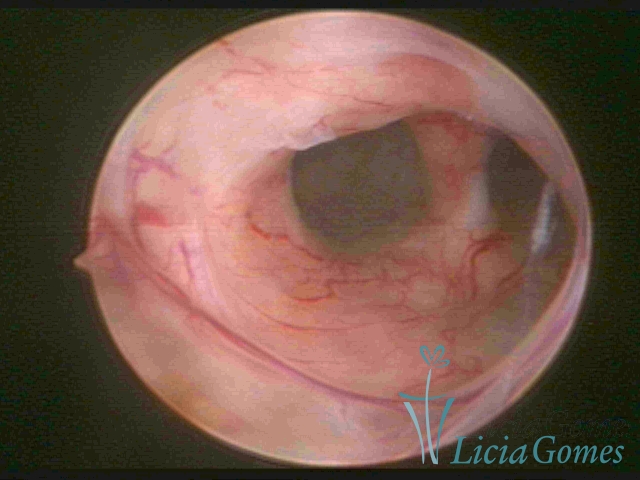

Útero septado

×